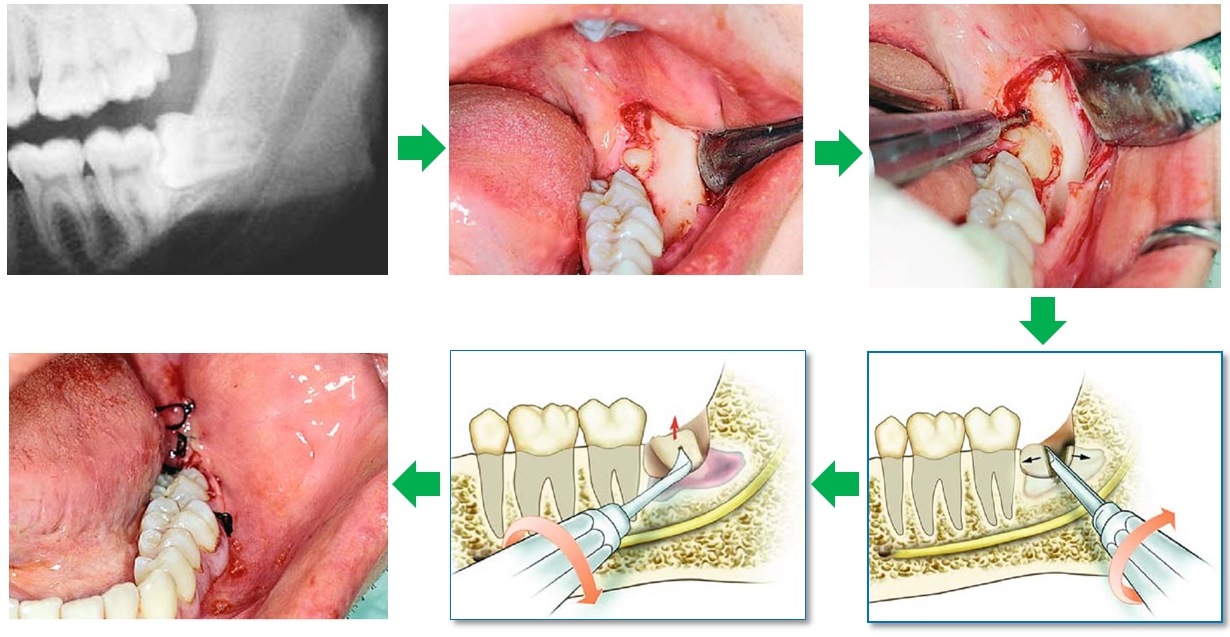

Răng khôn hay còn gọi là răng số 8 là chiếc răng mọc cuối cùng trên cung hàm. Thông thường, răng khôn mọc khi ở độ trưởng thành khoảng từ 17 đến 25 tuổi. Do mọc muộn khi xương hàm đã ổn định, khoảng trống bị hạn chế nên răng khôn dễ mọc lệch, mọc ngang, đâm vào răng số 7, hoặc chỉ trồi nhú lên một phần gây viêm nhiễm.

Chính vì vậy, mà răng khôn thường được xem là nguyên nhân gây đau nhức và các bệnh lý răng miệng phức tạp.

3. Nhổ Răng Khôn Có Nguy Hiểm Không?

Đây là câu hỏi khiến nhiều người thắc mắc và lo lắng khi muốn nhổ răng khôn. Nhổ răng khôn hoàn toàn an toàn, nếu được thực hiện tại địa chỉ uy tín như Nha Khoa Adent, với đội ngũ bác sĩ giàu kinh nghiệm và trang thiết bị công nghệ hiện đại.

Tuy nhiên, đối với những trường hợp vẫn có thể xảy ra biến chứng nếu quy trình thực hiện không đảm bảo:

• Ảnh hưởng dây thần kinh

Một số ít trường hợp răng khôn mọc ngầm sát dây thần kinh hàm dưới. Nếu thực hiện bởi bác sĩ tay nghề yếu có thể gây biến chứng như: khiến bệnh nhân bị tê môi, tê cằm tạm thời hoặc liệt cơ mặt.

• Thủng xoang hàm, hoặc gãy xương hàm

Hiếm gặp nhưng có thể xảy ra khi kỹ thuật thực hiện không đúng chuẩn, đặc biệt với răng khôn hàm trên.

Nếu bạn được chụp phim 3D và điều trị bởi bác sĩ có tay nghề và kinh nghiệm chuyên sâu. Tại Nha Khoa Adent, toàn bộ ca nhổ răng khôn và những phương pháp điều trị khác, đều được kiểm soát nghiêm ngặt nhằm đảm bảo an toàn tối đa cho khách hàng.